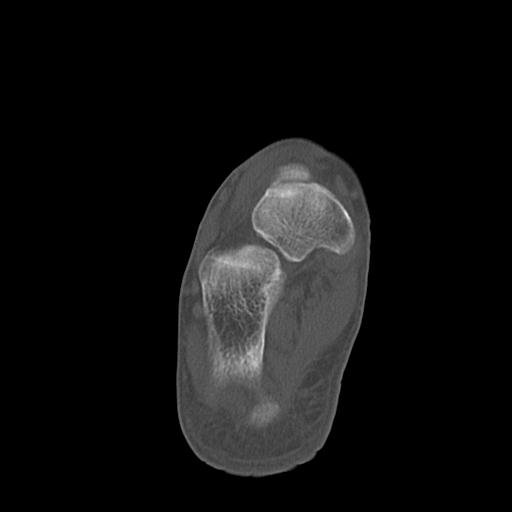

100612 11/25 1/20 右膝 2R 84歳女性 右TKA